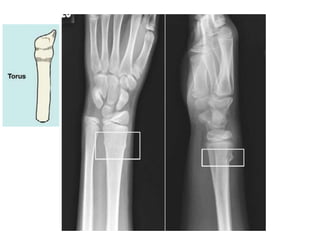

Osso de criança

Mais plásticos.

Periósteo espesso e firme, podendo não

Pode resultar em um torus ou em

fratura do tipo "galho verde“.

Osso de criança Maisplásticos. Periósteo espesso e firme, podendo não mais se ajustar ao osso fraturado. Pode resultar em um torus ou em fratura do tipo "galho verde“.